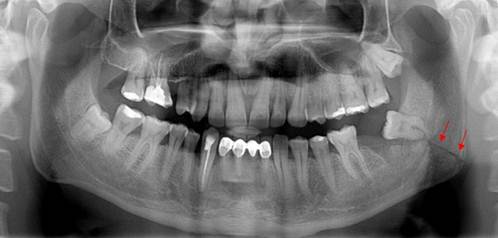

A 33-year-old male patient was referred to the Department of Oral Surgery, Faculty of Dentistry, Istanbul University, after an unsuccessful attempt to extract a partially erupted left third molar 1 week previously. The patient showed no significant disease or systemic condition. A panoramic radiograph and a volumetric tomographic scan showed an oblique and unfavorable fracture line on the left mandible that extended from the tooth roots to the mandibular angle (Figs. 4, 5).

Postoperative panoramic view of the patient showing the fracture line extending from the root to the mandibular angle.